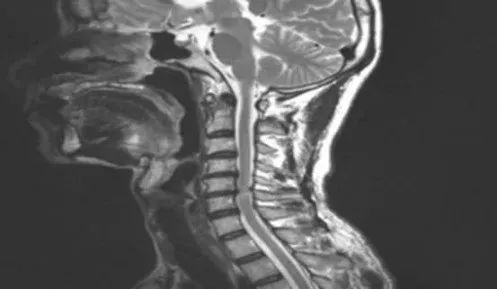

颈椎病又称颈椎综合征,是颈椎骨关节炎、增生性颈椎炎、颈神经根综合征、颈椎间盘脱出症的总称,是一种以退行性病理改变为基础的疾患。主要由于颈椎长期劳损、骨质增生,或椎间盘脱出、韧带增厚,致使颈椎脊髓、神经根或椎动脉受压,出现一系列功能障碍的临床综合征。表现为椎节失稳、松动;髓核突出或脱出;骨刺形成;韧带肥厚和继发的椎管狭窄等,刺激或压迫了邻近的神经根、脊髓、椎动脉及颈部交感神经等组织,引起一系列症状和体征。

颈椎病可分为:颈型颈椎病、神经根型颈椎病、脊髓型颈椎病、椎动脉型颈椎病、交感神经型颈椎病、食管压迫型颈椎病。